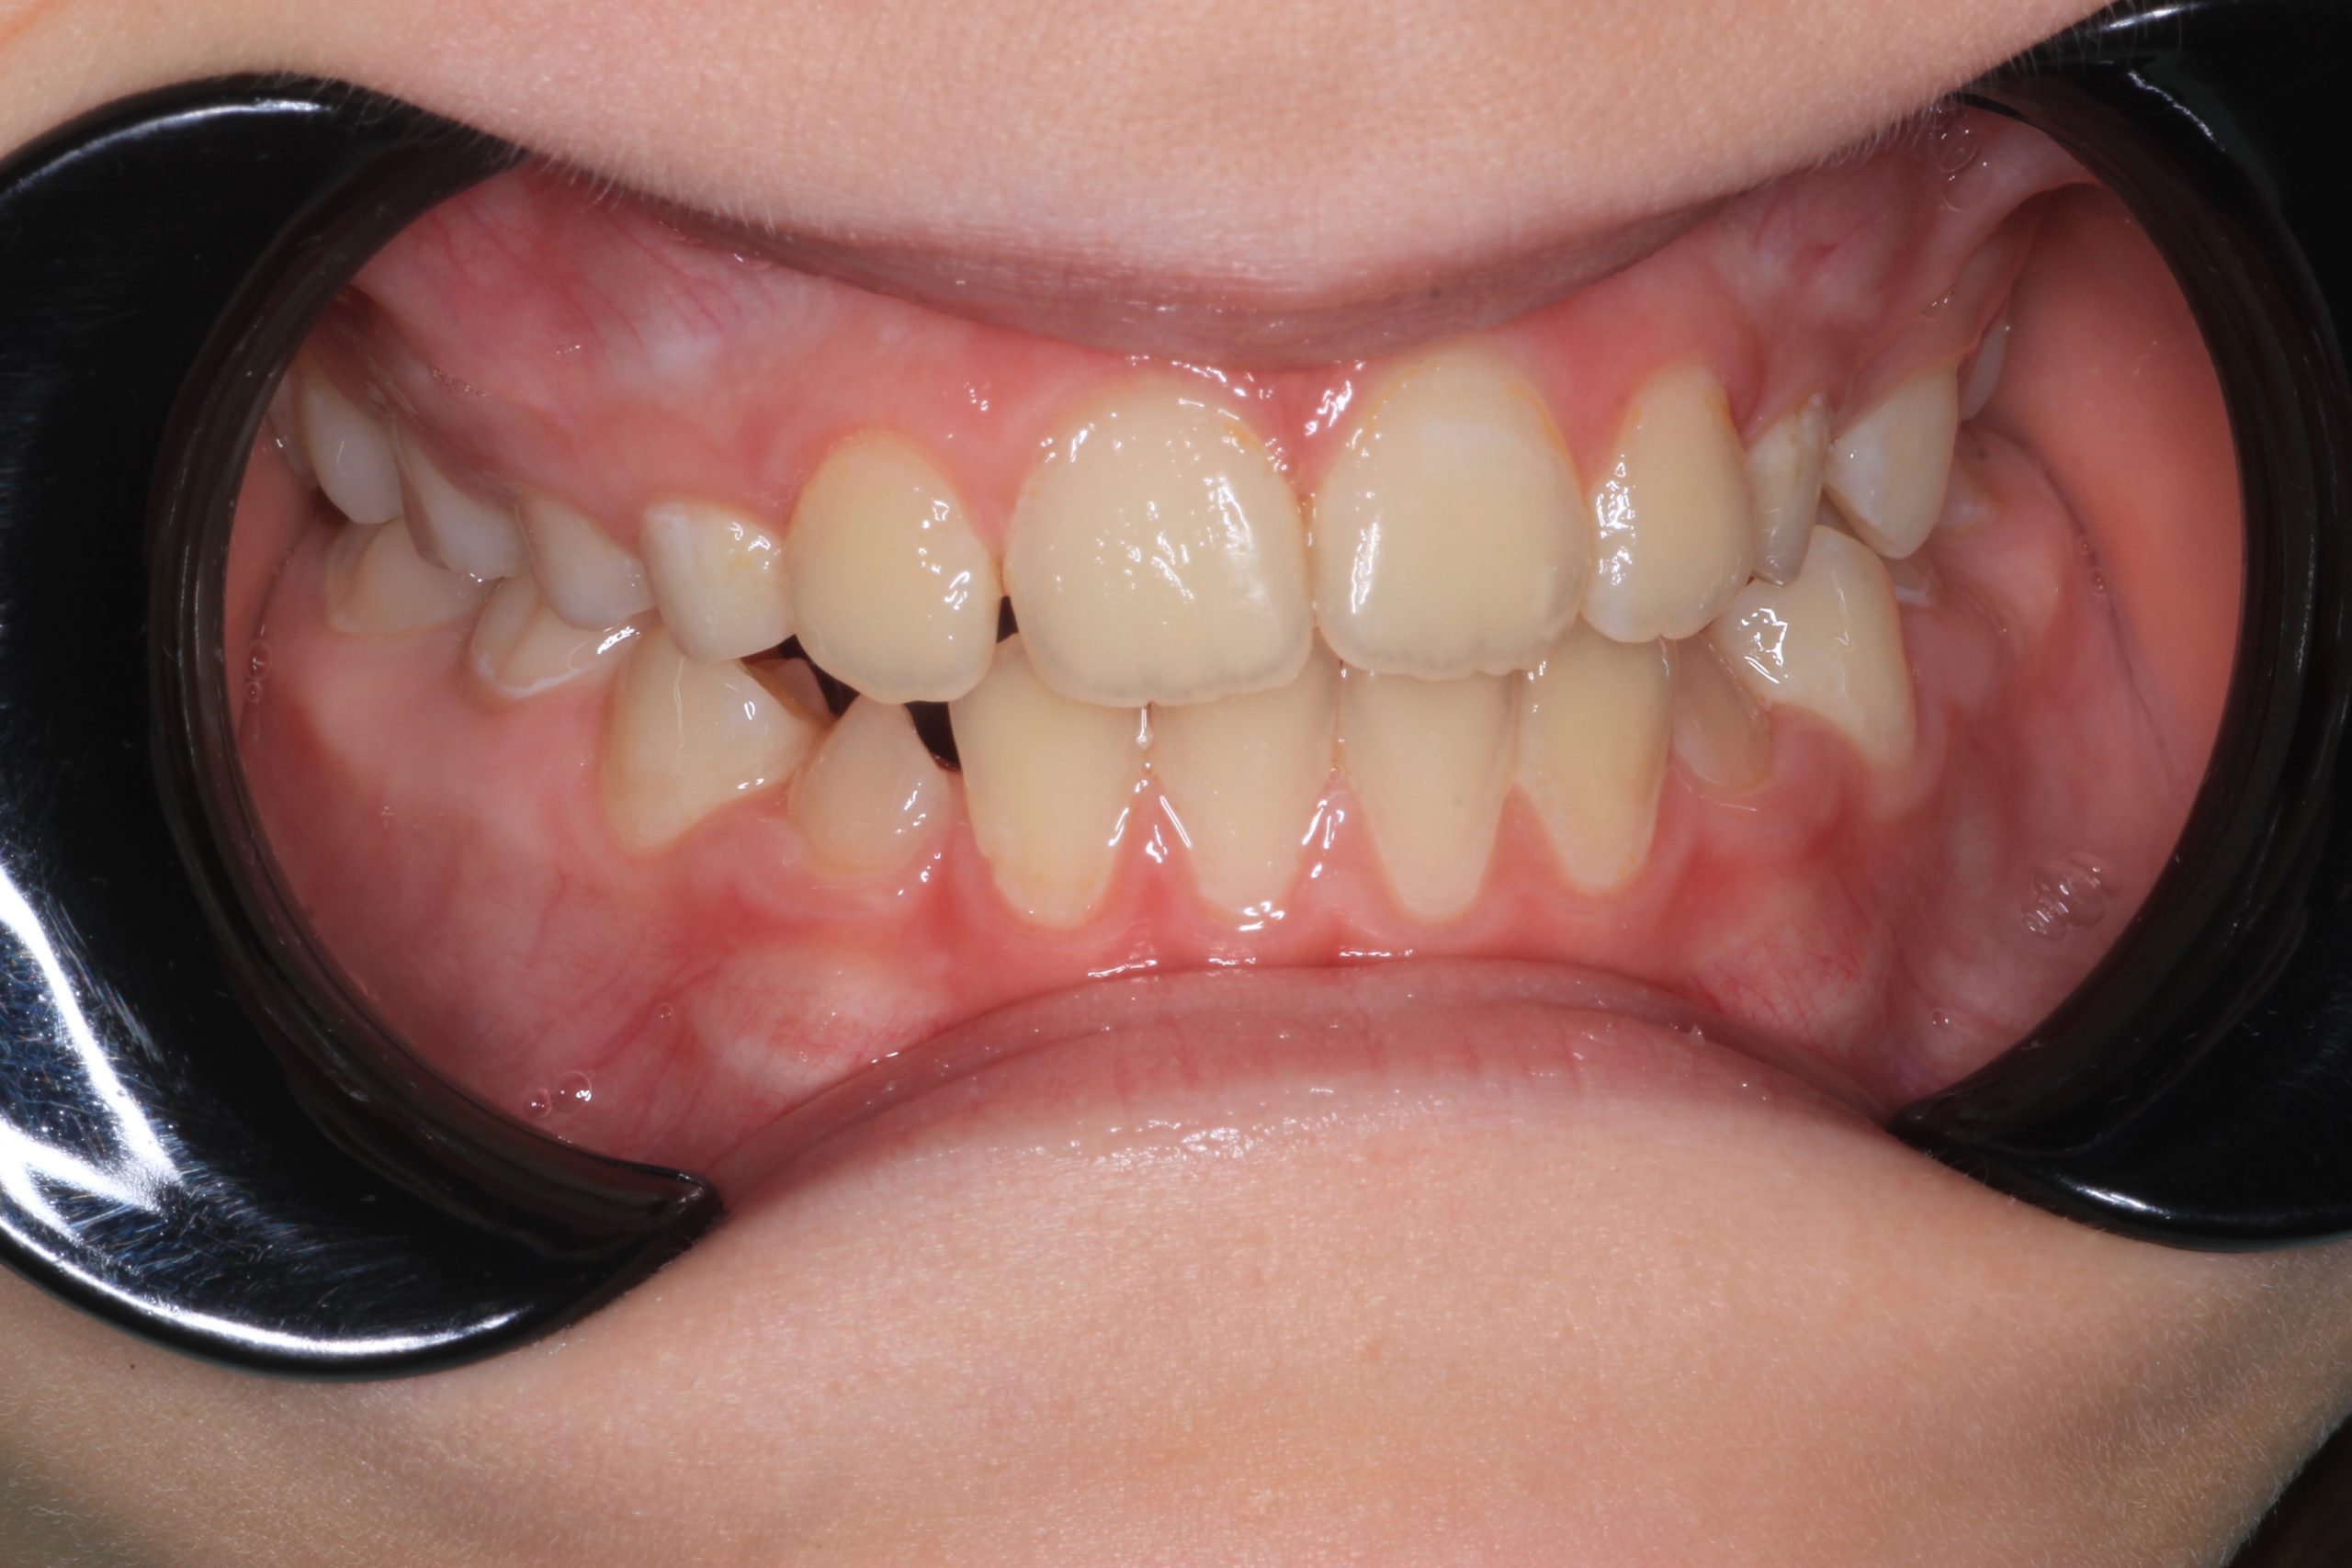

- Detailed Examination

We examine the condition of teeth, gums, and bite. - Plaque Disclosure with Special Indicators